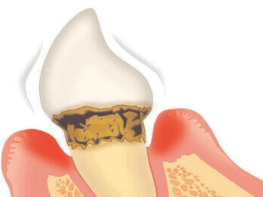

【軽度歯周炎】

歯茎が赤く腫れる

【中等度歯周炎】

歯槽骨が溶けて後退

歯と歯肉の間に汚れが溜まって歯肉が炎症を起こして赤く腫れている状態。歯周ポケットがやや深くなっています。この段階ではほとんど痛みはありませんが、歯磨きの際に出血することがあります。歯を支える歯槽骨は少し溶かされ始めています。

歯肉の炎症が更に進んでいき、歯周病菌が顎の骨にまで達してしまい、歯槽骨が溶け始めます。歯周ポケットが深くなり、歯がグラグラし始めます。歯肉からの出血だけではなく、歯と歯肉の間から膿が出る事もあります。